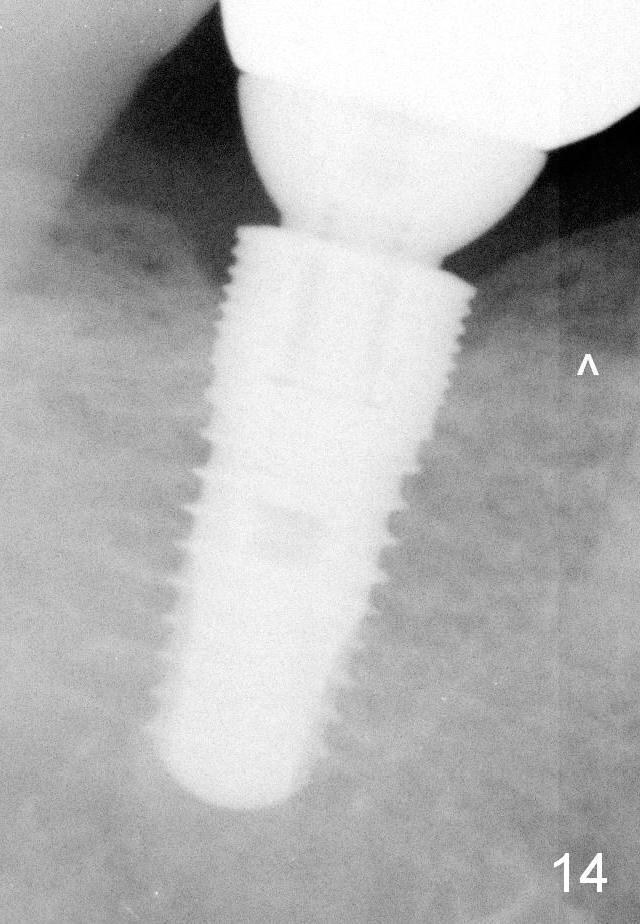

The patient returns for recall 9 months post cementation. His concern is inability to masticate hard on the right side. The tooth #29 has mobility I with bone loss (Fig.14 ^). There is no bone resorption around the implant.